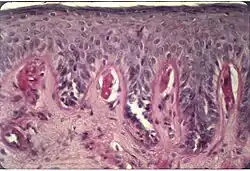

Protoporfíria eritropoiética (EPP) é uma forma de porfiria relativamente branda que surge a partir da deficiência da enzima ferroquelatase, levando a altos níveis anormais de protoporfirina nos tecidos do corpo. A severidade deste distúrbio varia significantemente entre cada pessoa. Protoporfiria eritropoiética (PPE) é uma desordem metabólica hereditária rara caracterizada por deficiência da enzima ferroquelatase (FEQ). Devido aos baixos níveis anormais desta enzima, quantidades excessivas de protoporfirina acumulam no plasma, células sanguínea e fígado. O principal sintoma desta desordem é hipersensibilidade da pele à exposição solar e alguns tipos de luz artificial, como luz fluorescente (fotosensibilidade). Após exposição à luz, a pele pode tornar-se pruriginosa e vermelha. Indivíduos afetados podem também experimentar sensação de queimação na pele. Mãos, braços e face são as áreas mais comumente afetadas. Algumas pessoas com protoporfíria eritropoiética podem também ter complicações relacionadas à função hepática e da vesícula biliar. Protoporfíria eritropoiética é herdada como traço genético autossômico dominante. Protoporfiria eritropoiética é um grupo de desordens conhecidas como porfirias. As porfírias são todas caracterizadas por níveis anormalmente altos de porfirinas no corpo devido a deficiências de certas enzimas. Há pelo menos sete tipos de porfíria. Os sintomas associados com vários tipos de porfíria diferem, dependendo de qual enzima específica é a deficiência. É importante notar que pessoas com um tipo de porfíria não desenvolve qualquer um dos outros tipos.